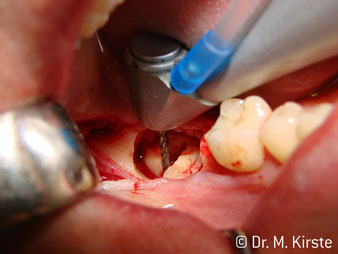

The 45° angle of the handpiece has been specially selected for its wide range of advantages. Colleagues who work in surgery, and for whom this handpiece was primarily developed, will soon appreciate the ability to work efficiently in very restricted spaces. In wisdom tooth extractions in particular (fig. 2) there is no need for large-scale spreading of the soft tissues in the cheek region (fig. 3). The design of the handpiece head combined with turning the head slightly during preparation allows work to be carried out quickly and safely in the retromolar region.

The professional design of the bearings inside the handpiece head guarantees quiet running of the bur; this makes for an impressively atraumatic cut in the separation of tooth and root (fig. 4-9).

The 45° contra-angle handpiece is very comfortable to hold. You notice almost straightaway that the working head mimics the angle of your index finger and, as such, the desired movement is simply transferred a couple of imaginary centimetres parallel to the tip. (Fig. 1)”

Fig. 1